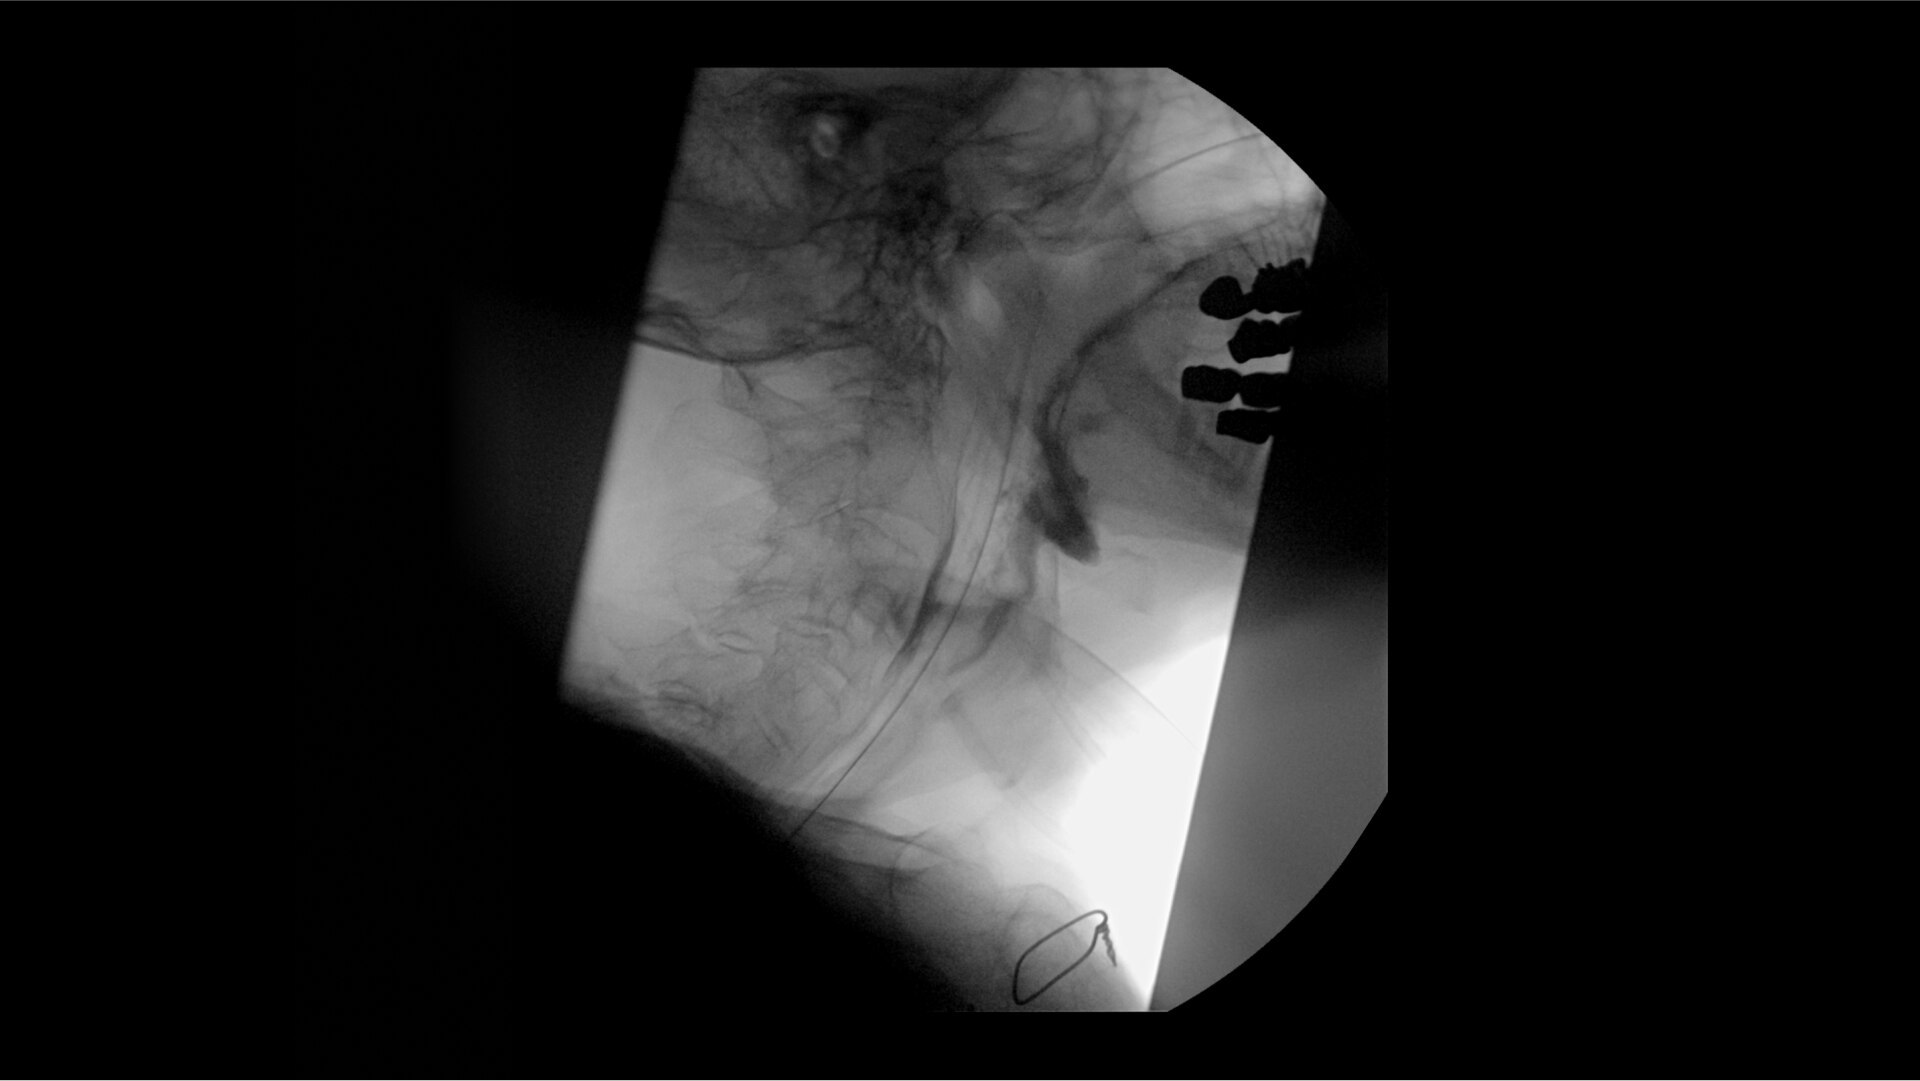

Clearly visualize the GI tract of patients, regardless of size, during a wide range of endoscopic procedures, including ERCP. OEC C-arms offer amazing image quality at low dose and provide enhancements for clear visualization during movement in soft tissue, such as during guidance of low-density drainage tubes or thin biopsy brushes. A large, clear display with comfortable viewing enables effortless workflow.

See detail 1 for 1 from detector to a 4K UHD display for stunning image quality and visualization of low density drainage tubes and thin biopsy brushes.

With OEC Elite CFD, the General HD preset profile optimizes to present high contrast, enhanced edge images to optimally see small detail such as stones in pancreatic duct.